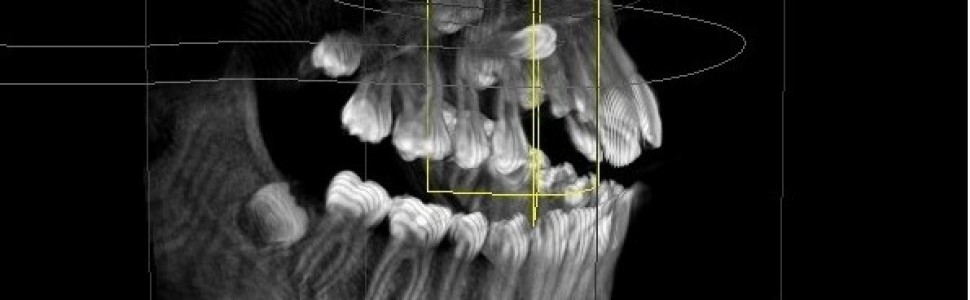

Torbiele zawiązkowe to drugie co do częstości występowania (po korzeniowych) tego typu struktury, stanowiące 24% wszystkich torbieli prawdziwych szczęk. Są jednymi z najczęściej występujących torbieli zębopochodnych szczęk związanymi z koronami zębów stałych, zwłaszcza z zatrzymanymi trzecimi zębami trzonowymi żuchwy. Występowanie obustronnych i mnogich torbieli jest związane z wieloma zespołami chorobowymi, na przykład dysplazją obojczykowo‑czaszkową, zespołem Gorlina. Torbiele zawiązkowe charakteryzują się powolnym i bezbolesnym wzrostem.

Dentigerous cysts are the second most common odontogenic cysts after radicular ones, accounting for approximately 24% of all true cysts of the jaw. Dentigerous cysts are one of the most common odontogenic cysts of the jaws, being associated with the crowns of permanent teeth, especially unerupted mandibular third molars. Bilateral and multiple cysts are usually found in connection with a number of syndromes that include cleidocranial dysplasia and Gorlin syndrome. Dentigerous cysts are characterized by slow, painless growth.